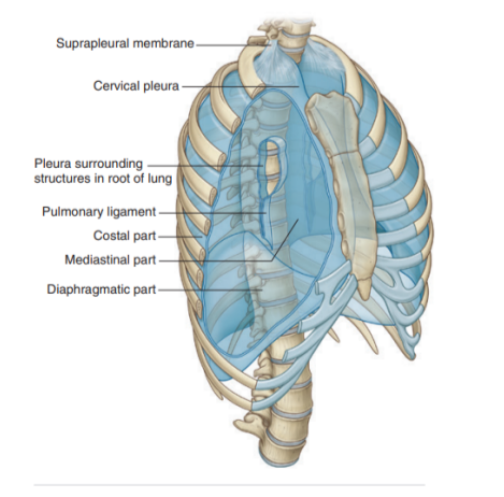

Specificities about the parietal pleura

Pleura related to the ribs and intercostal spaces — called costal part

Pleura covering the diaphragm — diaphragmatic part

Pleura covering the mediastinum — mediastinal part

Pleura lining the cervical extension of the pleural cavity — cervical pleura

(dome of pleura or pleural cupola)

Suprapleural membrane

Covers superior surface of cervical pleural cavity

The connective tissue membrane is laterally attached to the medial margin of the first rib & behind to the transverse process of vertebra CVII

Receives fibers from the scalene muscles — functions to keep the membrane under tension

Supra pleural muscles provide apical support for the pleural cavity in the root of the neck